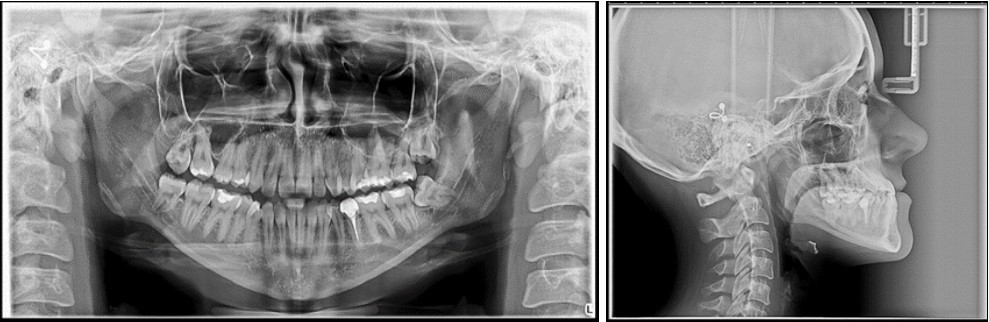

The panoramic radiograph examination showed impacted bilateral mandibular third molars, and one maxillary third molar.Cephalometric analysis disclosed a skeletal class III (ANB -5 degrees), with a retruded maxilla and a protruded mandible (SNA 78 degrees and SNB 83 degrees). The patient is a hyperdivergent type, with FMA 30 degrees and IMPA 77 degrees, which suggests retruded lower incisors. Examination of soft tissue on the profile radiograph shows a concave profile and a protruded lower lip. (Figure 3).

Figure 3.Initial panoramic and lateral cephalometric radiographs

Initial panoramic and  lateral cephalometric radiographs